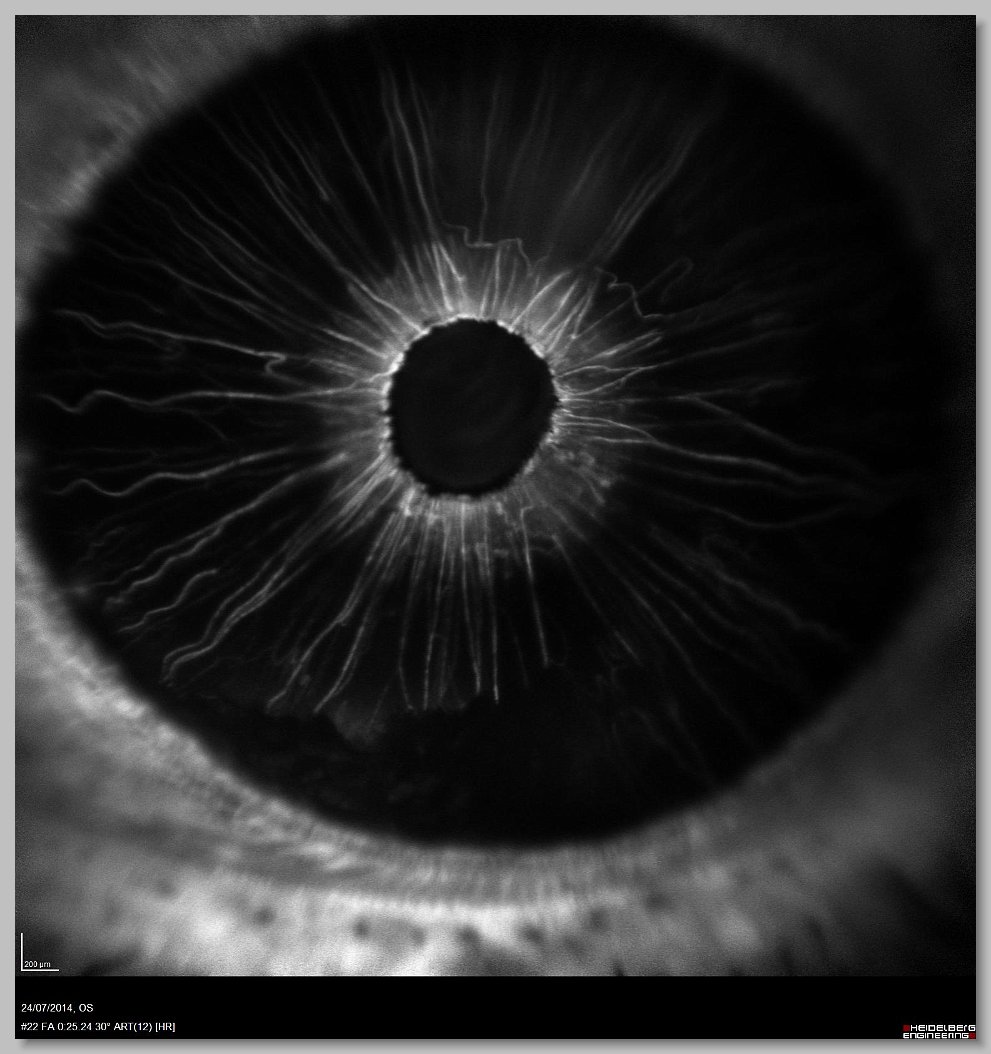

OCT 005 OCT 006 FA 000 FA 001

FA 002 FA 003 FA 004 FA 005

FA 006